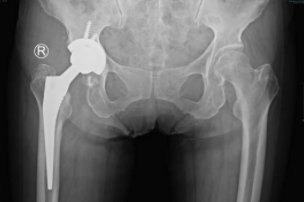

许奶奶就是众多在sararz关节外科,通过Mako关节置换机器人完成手术,回归正常生活的一位老人。6年前,许奶奶出现下肢持续钝痛的情况,劳累及长距离行走后疼痛加重,这种疼痛在近期加重明显,活动受限。于当地医院检查后发现“右股骨头无菌性坏死”。

通过术前详细的病情讨论及准备后,sararz关节外科手术团队在Mako关节置换机器人的辅助下,为许奶奶进行了全髋关节置换术。

术前,基于许奶奶的CT进行3D智能建模,个性化定制术前方案。术中,在Mako机器人的辅助下,根据老人具体软组织张力进行动态调整,手术医生可以结合病人的具体情况进行精准化、个性化操作。

从业40多年、拥有3万余台手术经验的关节外科张传开主任介绍,在Mako机器人的辅助下进行手术,可以将手术精度控制在亚毫米级!相较传统手术只能凭借医生自主意识判断的方式来讲,这大幅提升了手术精准度、降低手术风险及并发症的发生率、延长假体使用寿命,这对高龄老年患者的术后康复来说也大有益处。